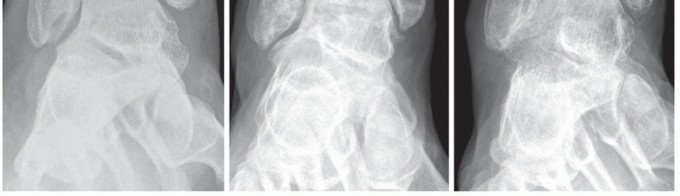

FIG 2 • Incompetence of the deltoid ligament. A. Distinct instability: AP weight-bearing radiograph shows a gapping of less than 5 degrees of the medial tibiotalar joint. B. Moderate instability: AP weight-bearing radiograph shows a gapping of 5 to 11 degrees of the medial tibiotalar joint. C. Severe instability: AP weight-bearing radiograph shows a gapping of more than 11 degrees of the medial tibiotalar joint.*

Acute injury: Plain radiographs, including anteroposterior (AP) and lateral views, should be obtained to rule out bony avulsion fractures or associated injuries.

Chronic injury: Plain weight-bearing radiographs, including AP views of the foot and ankle (FIG 2), a lateral

view of the foot, and a hindfoot alignment view,13 should be obtained to rule out old bony avulsion fractures, secondary deformities of the foot (eg, valgus malalignment of the heel, dislocation at the talonavicular joint), and tibiotalar alignment (eg, medial gapping of the joint due to incompetence of the deltoid ligament).